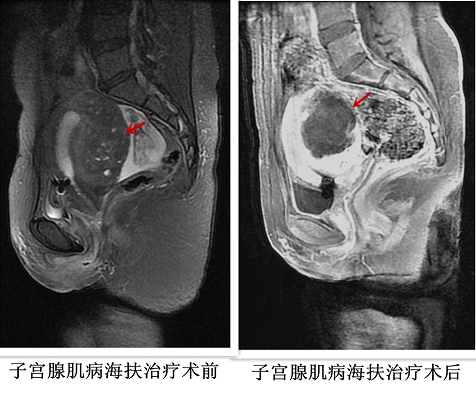

介入超声科隶属于中国人民解放军总医院(301医院)内科临床部肿瘤中心,专业于多种微创介入技术和实体肿瘤的消融治疗,是具有独立的病房和门诊的新型临床科室,开展了几乎所有热消融技术的临床应用,拥有微波消融治疗仪、射频消融治疗仪、激光消融治疗仪、JC型高强度聚焦超声肿瘤治疗系统等热消融治疗设备,以及多台高档超声仪。成功开展多种实体肿瘤的热消融治疗,主要包括:肝脏肿瘤、肾脏肾上腺肿瘤、甲状腺肿瘤、骨肿瘤、胰腺癌、乳腺肿瘤、软组织肿瘤、子宫肌瘤、子宫肌腺症以及各种腹膜后原发和转移癌等多种良性、恶性肿瘤,均取得了良好的临床疗效,积累了丰富的治疗经验,年治疗患者超过1000例次。曾获得多项国家、科技部、北京市和军队的基金资助,在国内外发表100多篇科技论文,并多次获得国家、北京市和军队科技进步奖及医疗成果奖。

高强度聚焦超声消融治疗是利用超声机械波经过精准聚焦后在很小的焦点处达到60℃-100℃的高温,非侵入性地治疗实体肿瘤的局部热消融治疗方法,使肿瘤组织达到凝固性坏死的病理变化,坏死的组织可逐渐被纤维化,体积缩小,症状缓解或甚至消失,达到治愈或姑息性治疗的目的。也可以用于放疗和化疗的热辅助治疗,能够增加肿瘤细胞对放射线和肿瘤药物的敏感性,提高临床疗效。

1.腹部的实体肿瘤(肝脏肿瘤、胰腺肿瘤、软组织肿瘤、子宫肌瘤、子宫肌腺病以及各种腹膜后原发和转移癌等);